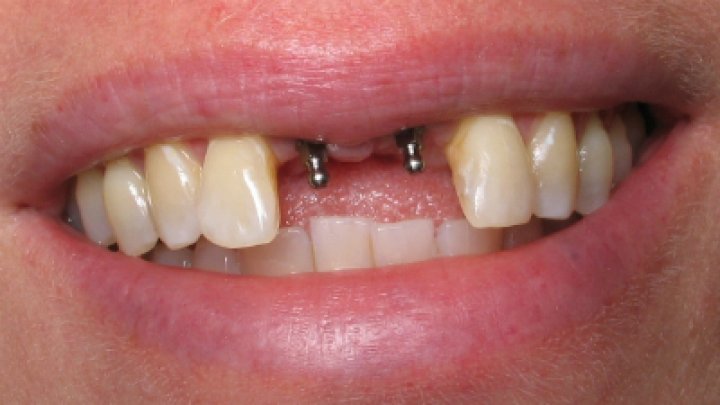

يتم إجراء عمليات الزرع في مراكزنا من قبل فريق من أخصائي زراعة الأسنان ذوي المهارات العالية وأطباء الأسنان التجميليين للحصول على دقة جراحية متميزة وجماليات ممتازة للابتسامة

يترأس مراكزنا فريق مختار بعناية من خبراء زراعة الأسنان. وبعد عملية الزرع يتم تركيب التيجان والجسور ، والتي يتم تصميمها بأقصى قدر من الدقة والجمالية لمنحك الابتسامة المثالية.

يتم تخطيط وتنفيذ إجراء زراعة الأسنان بعناية لضمان أن ترميم الأسنان يبدو طبيعيًا في الشكل واللون والمكان. نعطي الأولوية لراحة مرضانا بالإضافة إلى الجماليات. وهذا يتطلب مزيجًا مثاليًا من العبقرية الفنية والجراحية. لذلك ، يتم تنفيذ جميع حالات الزرع لدينا من قبل فريق من أطباء الأسنان التجميليين وأخصائي زراعة الأسنان.